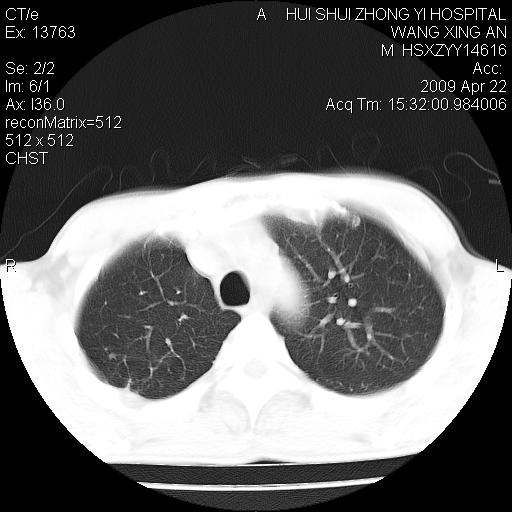

标题: CT19534:患者男、46岁咳嗽、胸痛半月。 [打印本页]

标题: CT19534:患者男、46岁咳嗽、胸痛半月。

1、右下肺中央型肺癌并右肺转移,右肺下叶不张。(右肺有结节影)。

1、右下肺中央型肺癌并右肺转移,右肺下叶不张。(肿块围绕右肺下叶支气管生长,致管腔闭塞右肺下叶不张;右肺有结节影)。

3、右中上肺陈旧性肺结核(右肺见纤维化病灶及点状钙化)。

1。右下肺中央型肺癌并肺转移,右肺下叶不张。(两肺都有结节影)。

1)右肺中间段支气管癌并右肺下叶肺不张。2)右肺上叶、两肺下叶背段感染性病变。3)右侧少量胸腔积液。